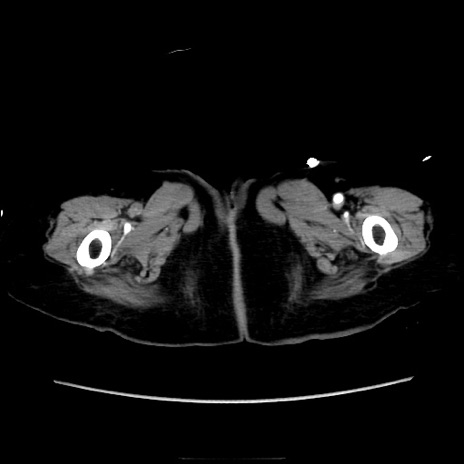

症例40(横断像)

【症例】90歳代女性

【主訴】腹痛・嘔吐

【現病歴】 食欲低下、嘔吐があり昨日他院受診。肺炎と診断され入院となる。入院後より腹部全体に圧痛あり。胃管留置され経過みていたが、症状持続するため、

当院転院となる。

【既往歴】胸椎圧迫骨折、胆石症

【身体所見】腹部:中央に激痛あり、圧痛あり、反跳痛不明

【データ】WBC 17100、CRP 18.82